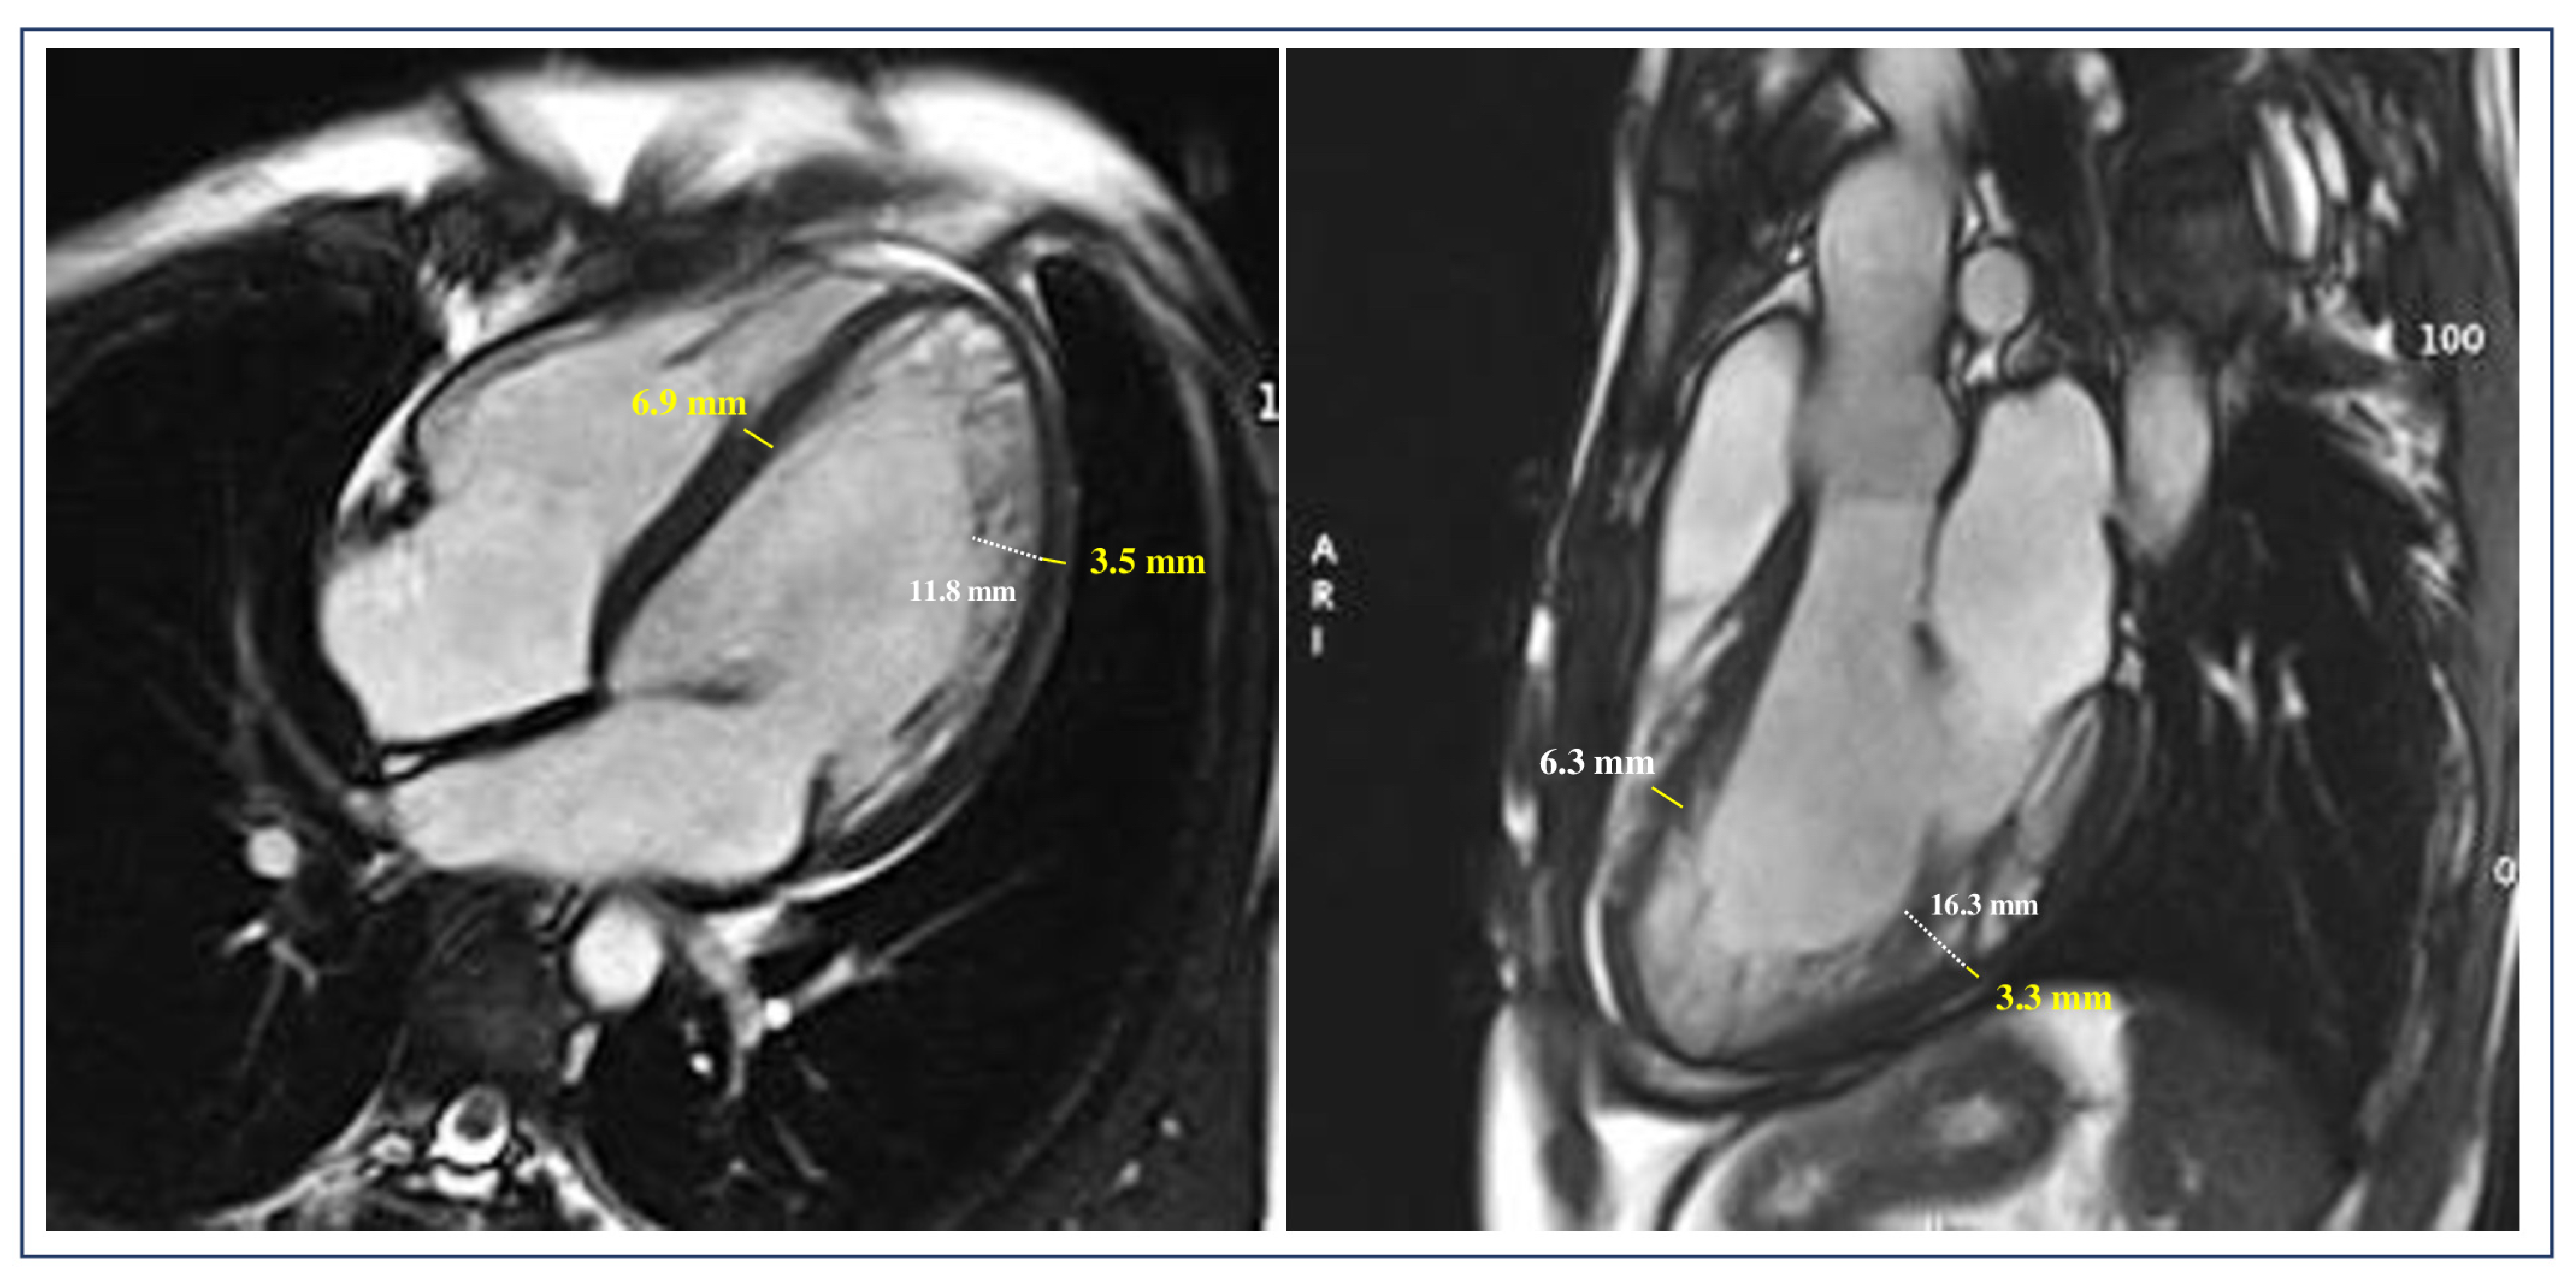

- De Lazzari, M.; Brunetti, G.; Frasson, E.; Zorzi, A.; Cipriani, A.; Migliore, F.; De Conti, G.; Motta, R.; Perazzolo Marra, M.; Corrado, D. Thinning of compact layer and systolic dysfunction in isolated left ventricular non-compaction: A cardiac magnetic resonance study. Int. J. Cardiol. 2024, 397, 131614. [Google Scholar] [CrossRef]